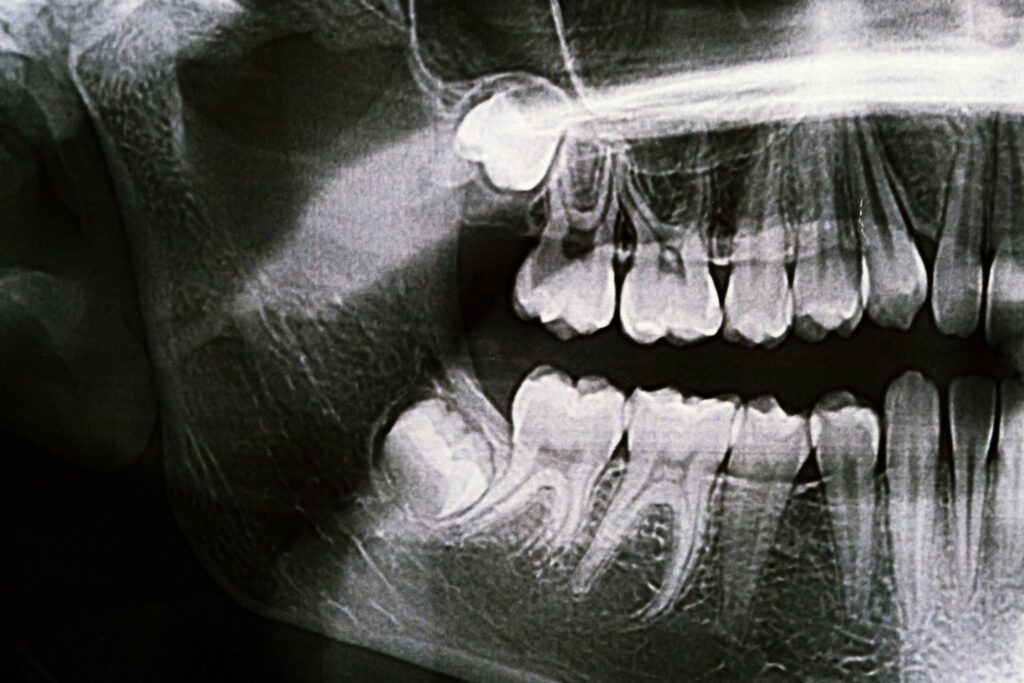

The average adult mouth is designed to hold around 28 teeth comfortably, but most adults end up with 32. The additional four teeth are called wisdom teeth or third molars. When there isn’t enough room for them, the wisdom teeth become blocked or impacted by the other teeth around them. This can become extremely traumatizing. If the wisdom tooth partially erupts, food can get trapped in the tissue surrounding it, which can lead to bacterial growth and possibly serious infection.

By removing wisdom teeth when a patient is a young adult, our dentists are able to prevent potential healing problems. When a person reaches the age of their mid-thirties, there are much higher risks involved in wisdom teeth removal. The best time to remove wisdom teeth is generally between the ages of fifteen to eighteen.